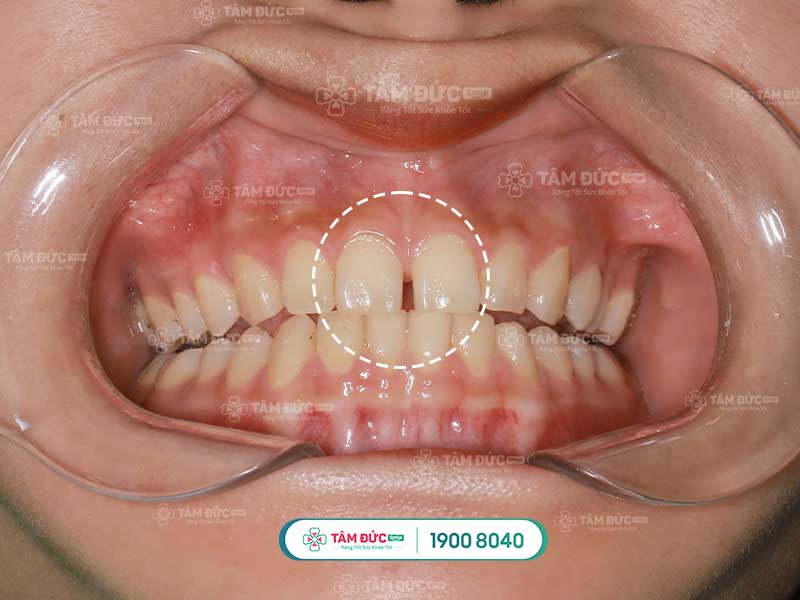

Răng cửa thưa là tình trạng lệch lạc khớp của những răng đứng trên cung hàm nhưng không sát với nhau mà tạo ra khe hở giữa những răng. Khe hở này có thể to hoặc nhỏ tùy thuộc và mức độ lệch lạc nặng hay nhẹ của răng trên cung hàm.

Răng cửa thưa làm thẩm mỹ khuôn mặt bị ảnh hưởng nhiều, gây tâm lý e ngại, kém tự tin khi cười nói, cười không tự nhiên. Đặc biệt những người giao tiếp nhiều sẽ gặp rào cản về phát âm và giảm hiệu quả thành công trong công việc. Theo tướng số, người răng thưa luôn khó giữ được tiền và để vụt mất nhiều cơ hội trong cuộc sống.

Răng cửa thưa ảnh hưởng đến thẩm mỹ